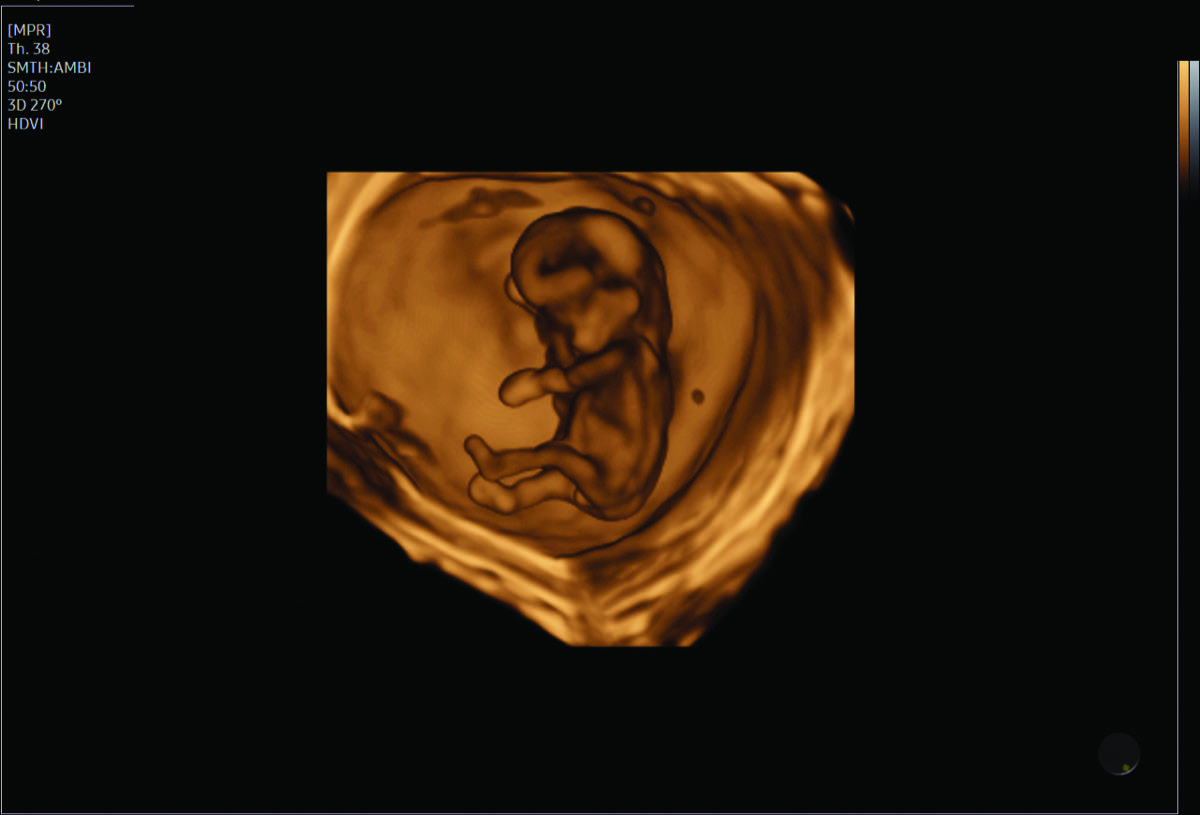

- Fetal anomalies